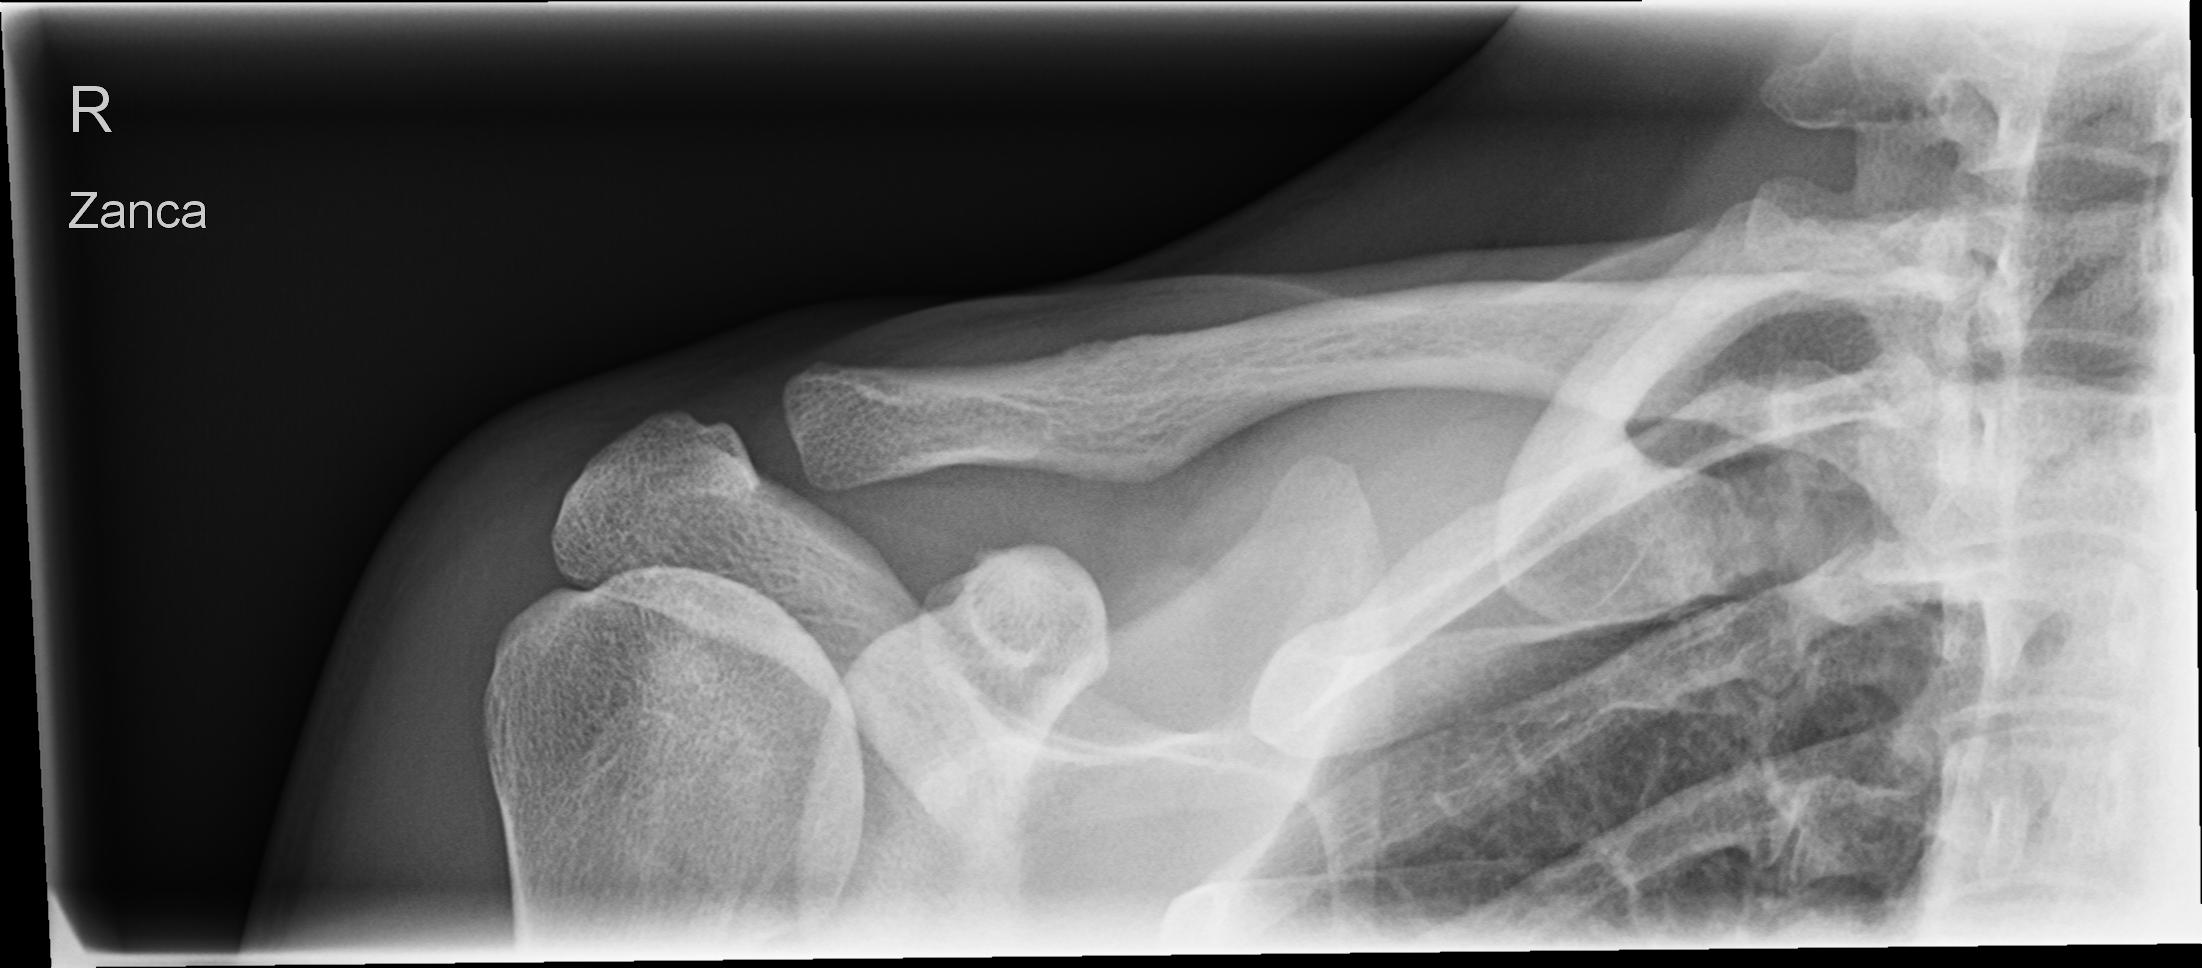

AC-Gelenk nach Zanca

Es wurden keine Bilder gefunden.

Technik

• FDA: 1,15 m

• Ausgangsformat: 18/24 quer

• mit Raster

• Röhrenkippung: 30°- 45° caudo-cranial

Lagerung

Rückenlage am Stativ oder liegend auf dem Tisch

Kopf zur gesunden Seite drehen

Arme parallel am Körper

Zentralstrahl

30-45° caudo-cranial gekippt, auf Höhe des Acromioclaviculargelenk.

Bemerkung

Atemphase: Der Patient hält den Atem an.

Qualitätskriterien

Gut beurteilbare Darstellung des ganzen Schlüsselbeins und des Acromioclaviculargelenkes.